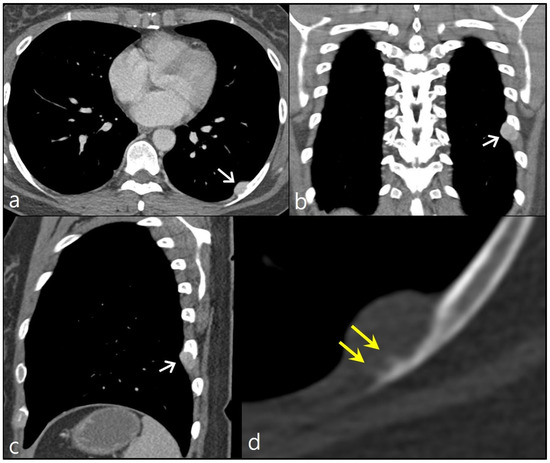

Figure 2.

(a) A high cellular spindle cell tumor was composed of pleomorphic hyperchromatic cells with lace-like woven bones (×200, H&E). (b) In some parts of the lesion, there was woven bone with endochondral ossification (arrowheads), suggestive of a high-grade osteosarcoma (×100, H&E). A minute segment of the tumorous lesion displayed a connection to the medullary cavity of the rib bone, suggestive of endosteal extension (highlighted in box in (c), ×10, H&E). Upon closer magnification, it was evident that cancerous cells were infiltrating into medullary trabeculae (encircled in (d), ×100, H&E).

We performed a video-assisted thoracoscopic excision of the nodule, along with adjacent ribs, for diagnostic and therapeutic purposes. Upon gross examination of the specimen, it was noted that the lesion abutted the eighth rib, with a very small portion of the nodule connected to the rib bone. Upon microscopic examination, the nodule was identified as a highly cellular spindle cell tumor. In a part of the lesion, woven bone with endochondral ossification was noted, suggestive of a high-grade osteosarcoma. A tiny part of the tumor was connected to the medullary cavity of the rib bone, indicating the potential presence of endosteal extension. Upon higher magnification, it was evident the malignant cells were infiltrating the medullary trabeculae (Figure 2). Based on pathologic findings, a diagnosis of high-grade surface osteosarcoma was established.